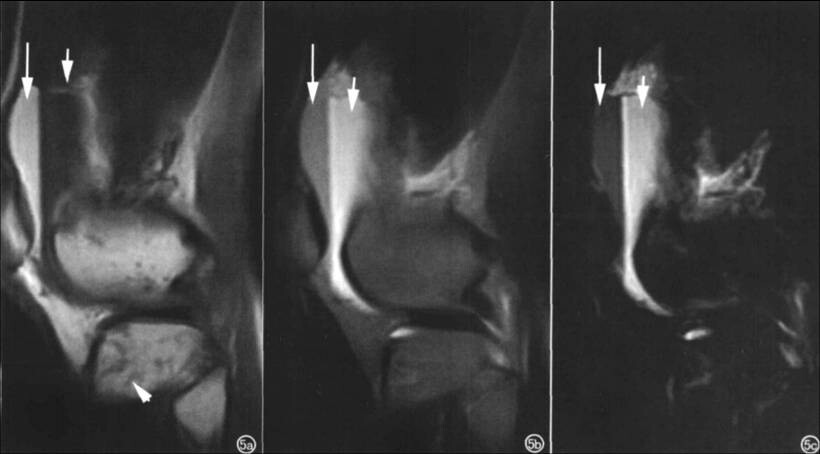

患者女,43岁,外伤后膝关节疼痛就诊!考虑创 伤 性 关 节 积 脂 血 征(TLH ),即创伤后关节囊内存在脂肪和血液, 可发生在全身受损伤的任何关节, X线平片、 超声、CT及 MR I均可检测 TLH。CT密度分辨率高, MRI组织分辨率高, 都可准确地反映TLH 的组成成分.